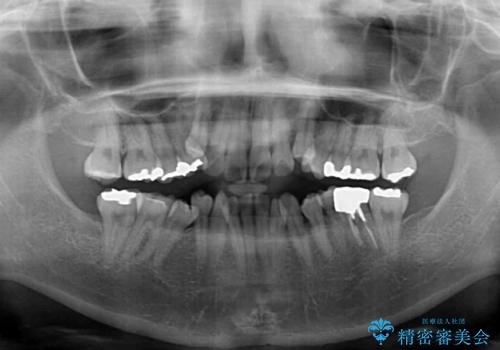

- 八重歯やデコボコを気にして来院された患者様です。

お住まいから船での通院となることから、補助装置を使用しながらインビザラインにて上下左右第一小臼歯4本を抜歯した矯正治療を行うこととしました。

マウスピース(インビザライン)はほとんど使用することができませんでしたが、補助装置により上顎の八重歯は改善しておいたので、ワイヤー装置ではスムーズに治療を終えることができました。